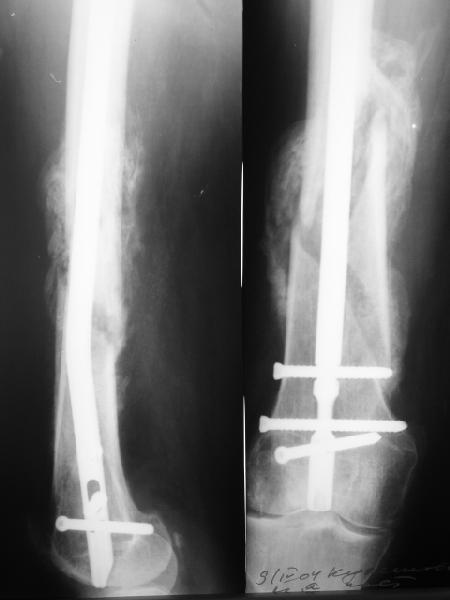

Антеградный остеосинтез при дистальных переломах бедра мы применяем давно, этот материал обобщен в канд. диссертации Александра Виноградского.

Предприятие ЦИТО выпускает доработанные нами гвозди, которые хорошо годятся для дистальных переломов, да и недороги. Можно вводть в дистальное овальное отверстие 3 винта, которые заклинивают друг друга.

Большеберцовые стержни отлично выполняют роль ретроградных бедренных. Конечно, которые не 9, а 12 мм в диаметре.

Примеры приложены.